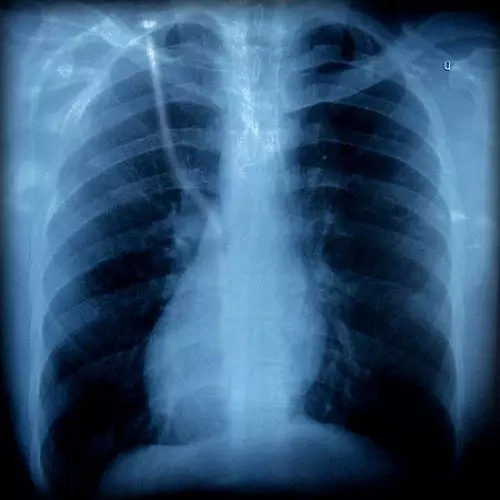

胸片有異

胸外科

咳嗽可以是由肺部腫瘤等疾病引起的,如果胸片或胸部CT上發(fā)現(xiàn)有可疑病變時,應該看看胸外科。一般,呼吸內科大夫也會幫忙轉診的。